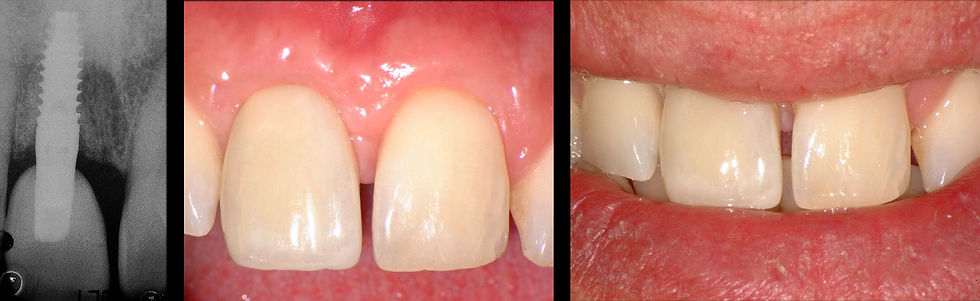

The pictures and the radiographs of the final restoration after 8 months from the implant insertion show a pleasant aesthetics, resulting from a correct balance between hard and soft tissues. These outcomes are possible thanks to the perfect adaptation of the periodontal area to the Prama implant neck.